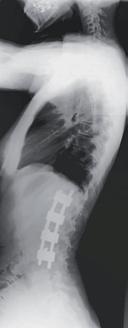

RYCINA 34.15.

Radiogram kręgosłupa w projekcji przednio-tylnej – stan pooperacyjny.